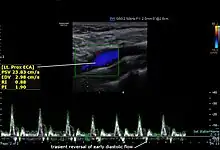

The condition and health of the external carotid arteries is usually evaluated using Doppler ultrasound, CT angiogram or phase contrast magnetic resonance imaging (PC-MRI). Typically, blood flow velocities in the external carotid artery are measured as peak systolic velocity (PSV) and end diastolic velocity (EDV).[4]

PSV values greater than 200 cm/s are considered to be predictive of more than 50% of external carotid artery stenosis.[5]